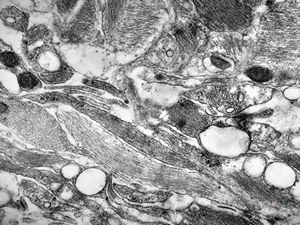

rabbit spinal cord trauma